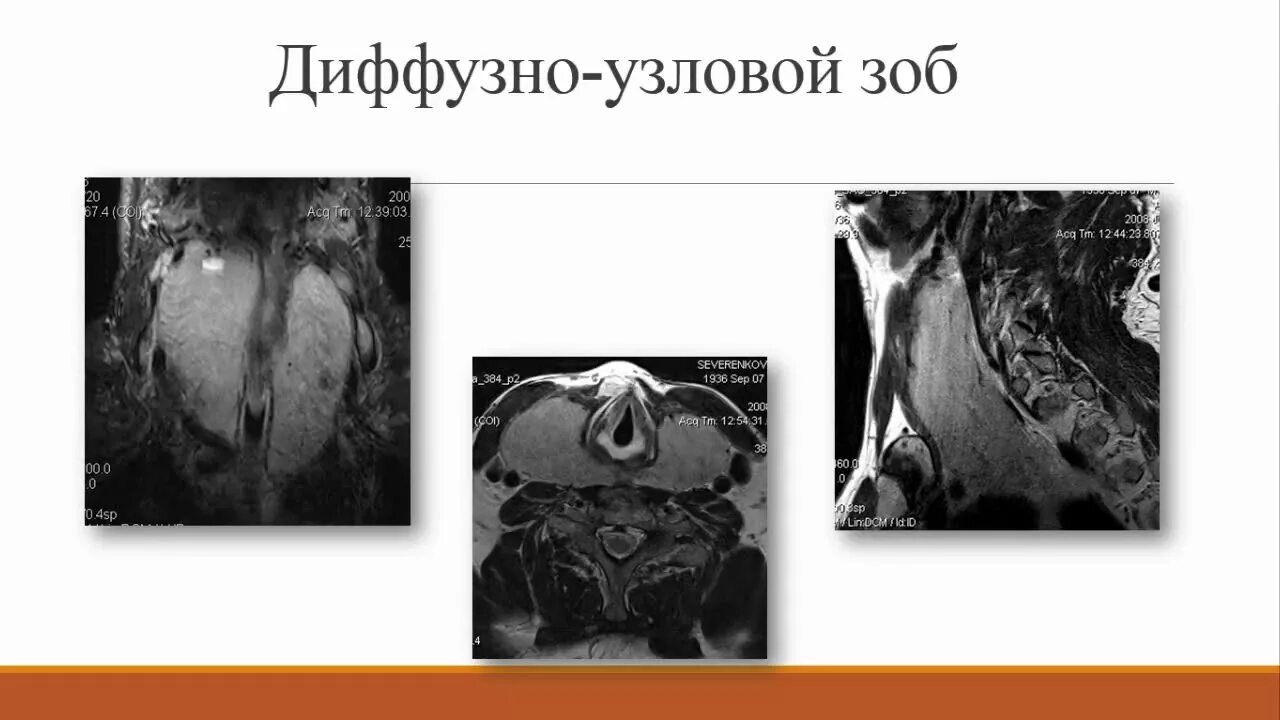

Диффузные л